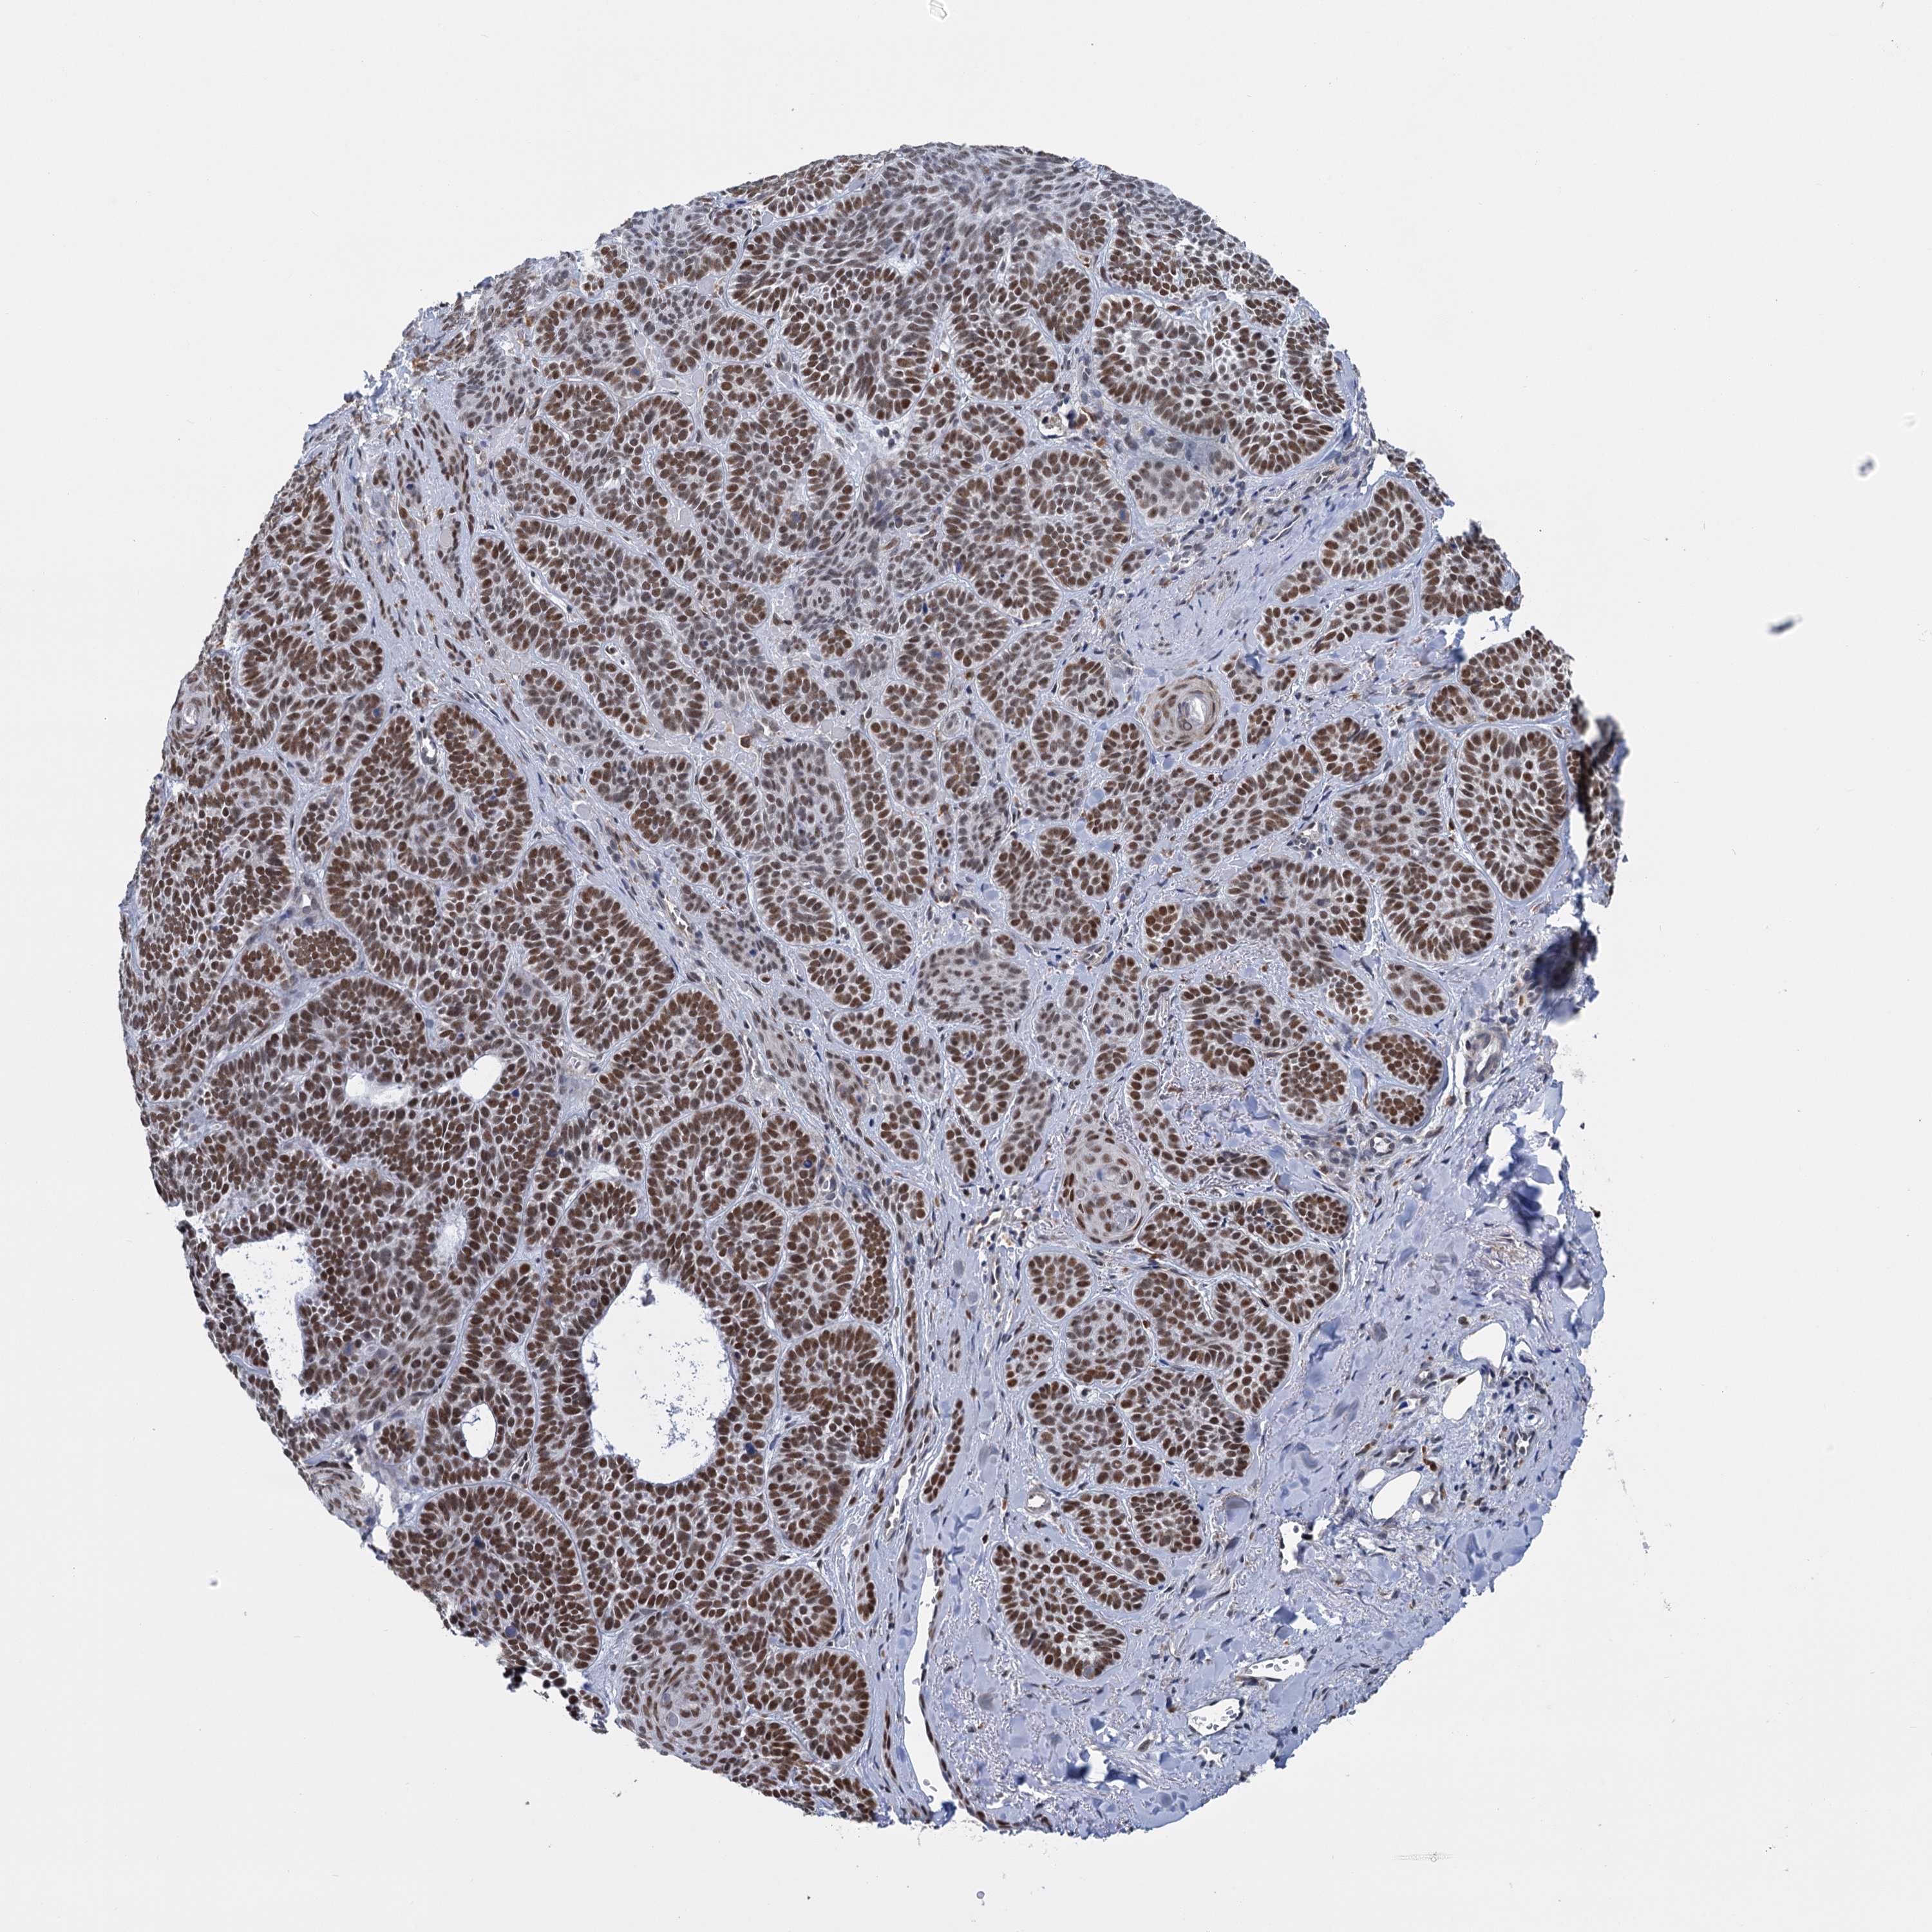

SKIN CANCER - Protein expressioni

A mouse-over function shows sample information and annotation data. Click on an image to view it in a full screen mode. Samples can be filtered based on level of antibody staining by selecting one or several of the following categories: high, medium, low and not detected. The assay and annotation is described here.

Antibody staining in the annotated cell types in the current human tissue is reported as not detected, low, medium, or high, based on conventional immunohistochemistry profiling in selected tissues. This score is based on the combination of the staining intensity and fraction of stained cells.

Each image is clickable and will lead to virtual microscopy that enables deeper exploration of all samples and also displays staining intensity scores, fraction scores and subcellular localization as well as patient and tissue information for each sample.

Antibody HPA038709

Staining

High

Intensity

Strong

Quantity

>75%

Location

Nuclear

Basal cell carcinoma